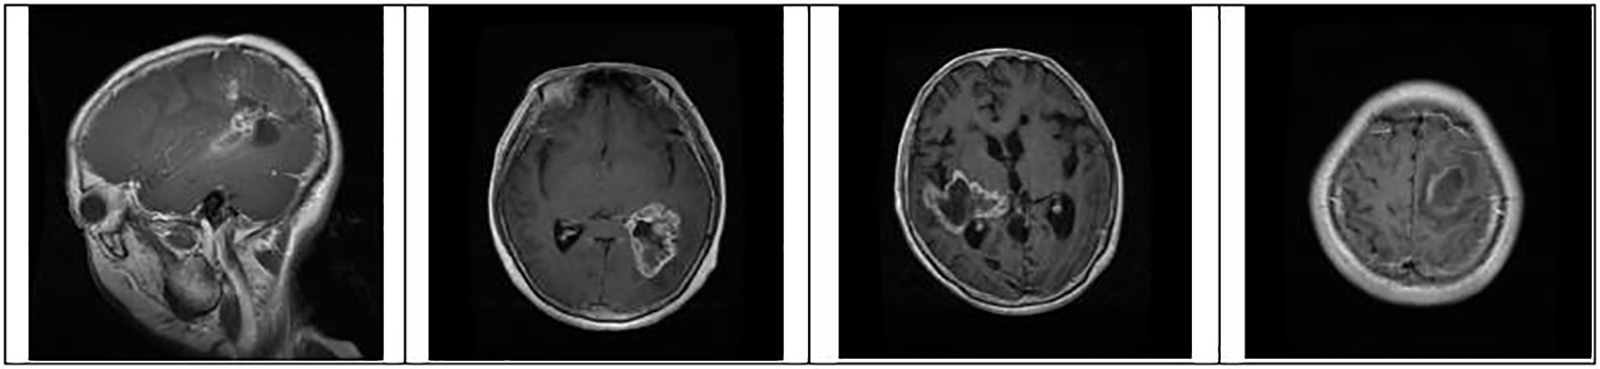

Figure 4: Identification of brain tumor-type glioma samples from the dataset for training and testing

where pc is a package configuration of brain tumor algorithm, mf is making the file of brain tumor, and m is brain tumor contour make. Figs. 4 to 6 represent three different types of brain tumors: glioma, meningioma, and pituitary. With algorithm 1, all said types were identified. The output of different kinds of brain tumor detection and its sample is represented in Figs. 4 to 6. Here glioma is a low-grade tumor, like a normal brain, with a similar texture and colour. Here intra-operative sampling and the enhanced visual tumor have been applied as glioma detection steps, as shown in Fig. 4. For meningioma detection, vision change, seizures, and confusion were checked with dura mater and pia mater, as shown in Fig. 5. Here DeepMedic architecture with t1 method for MRI image. The same further process is applied to pituitary tumors. The EDLA architecture process was applied, and results were generated.